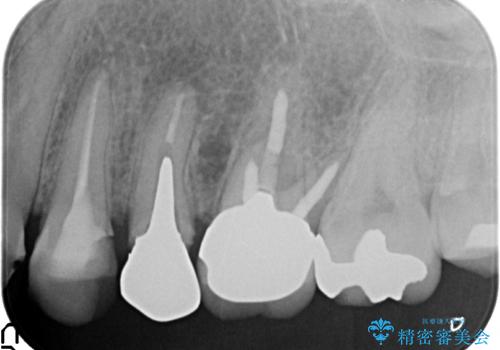

- 左上2番目の歯がグラグラするので診て欲しいといらっしゃった方の症例です。

左上2番目の歯は歯根が破折してため抜歯し、左上123のブリッジによる欠損補綴を行いました。

左上4、5番目の歯は根尖病変を認めたため再根管治療を行い、オールセラミッククラウンによる補綴を行いました。

なお左上4に関しては縁下歯質を改善するため、歯冠挺出を行っております。